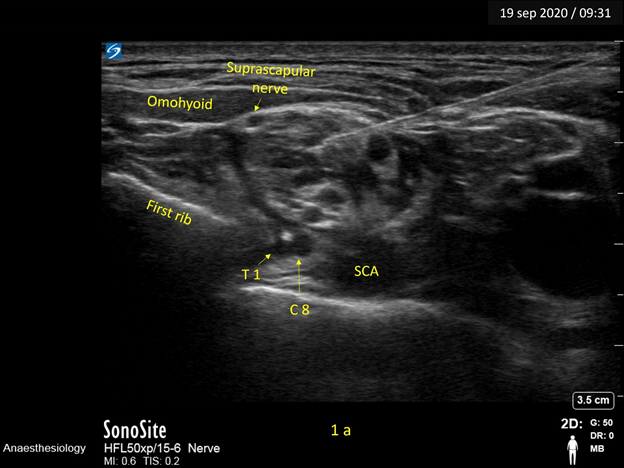

In Figure 1a, the needle tip is positioned in the centre of the “Bunch of grapes” and illustrates the LA spread obtained with the “Centre-cluster” injection technique.1 An important drawback with centre-cluster injection was ulnar sparing. In this image we can well appreciate that though the LA spread has occurred across a major part of the plexus, the two hypoechoic structures representing the neural elements of C8 and T1 roots at the 6’0 clock position to the plexus are spared.

Figure 1a Image depicts the needle tip at the center of the cluster – the ‘Centre-cluster injection’ technique. The local anaesthetic is seen to bathe a major portion of the plexus, but the C8, T1 roots are spared.